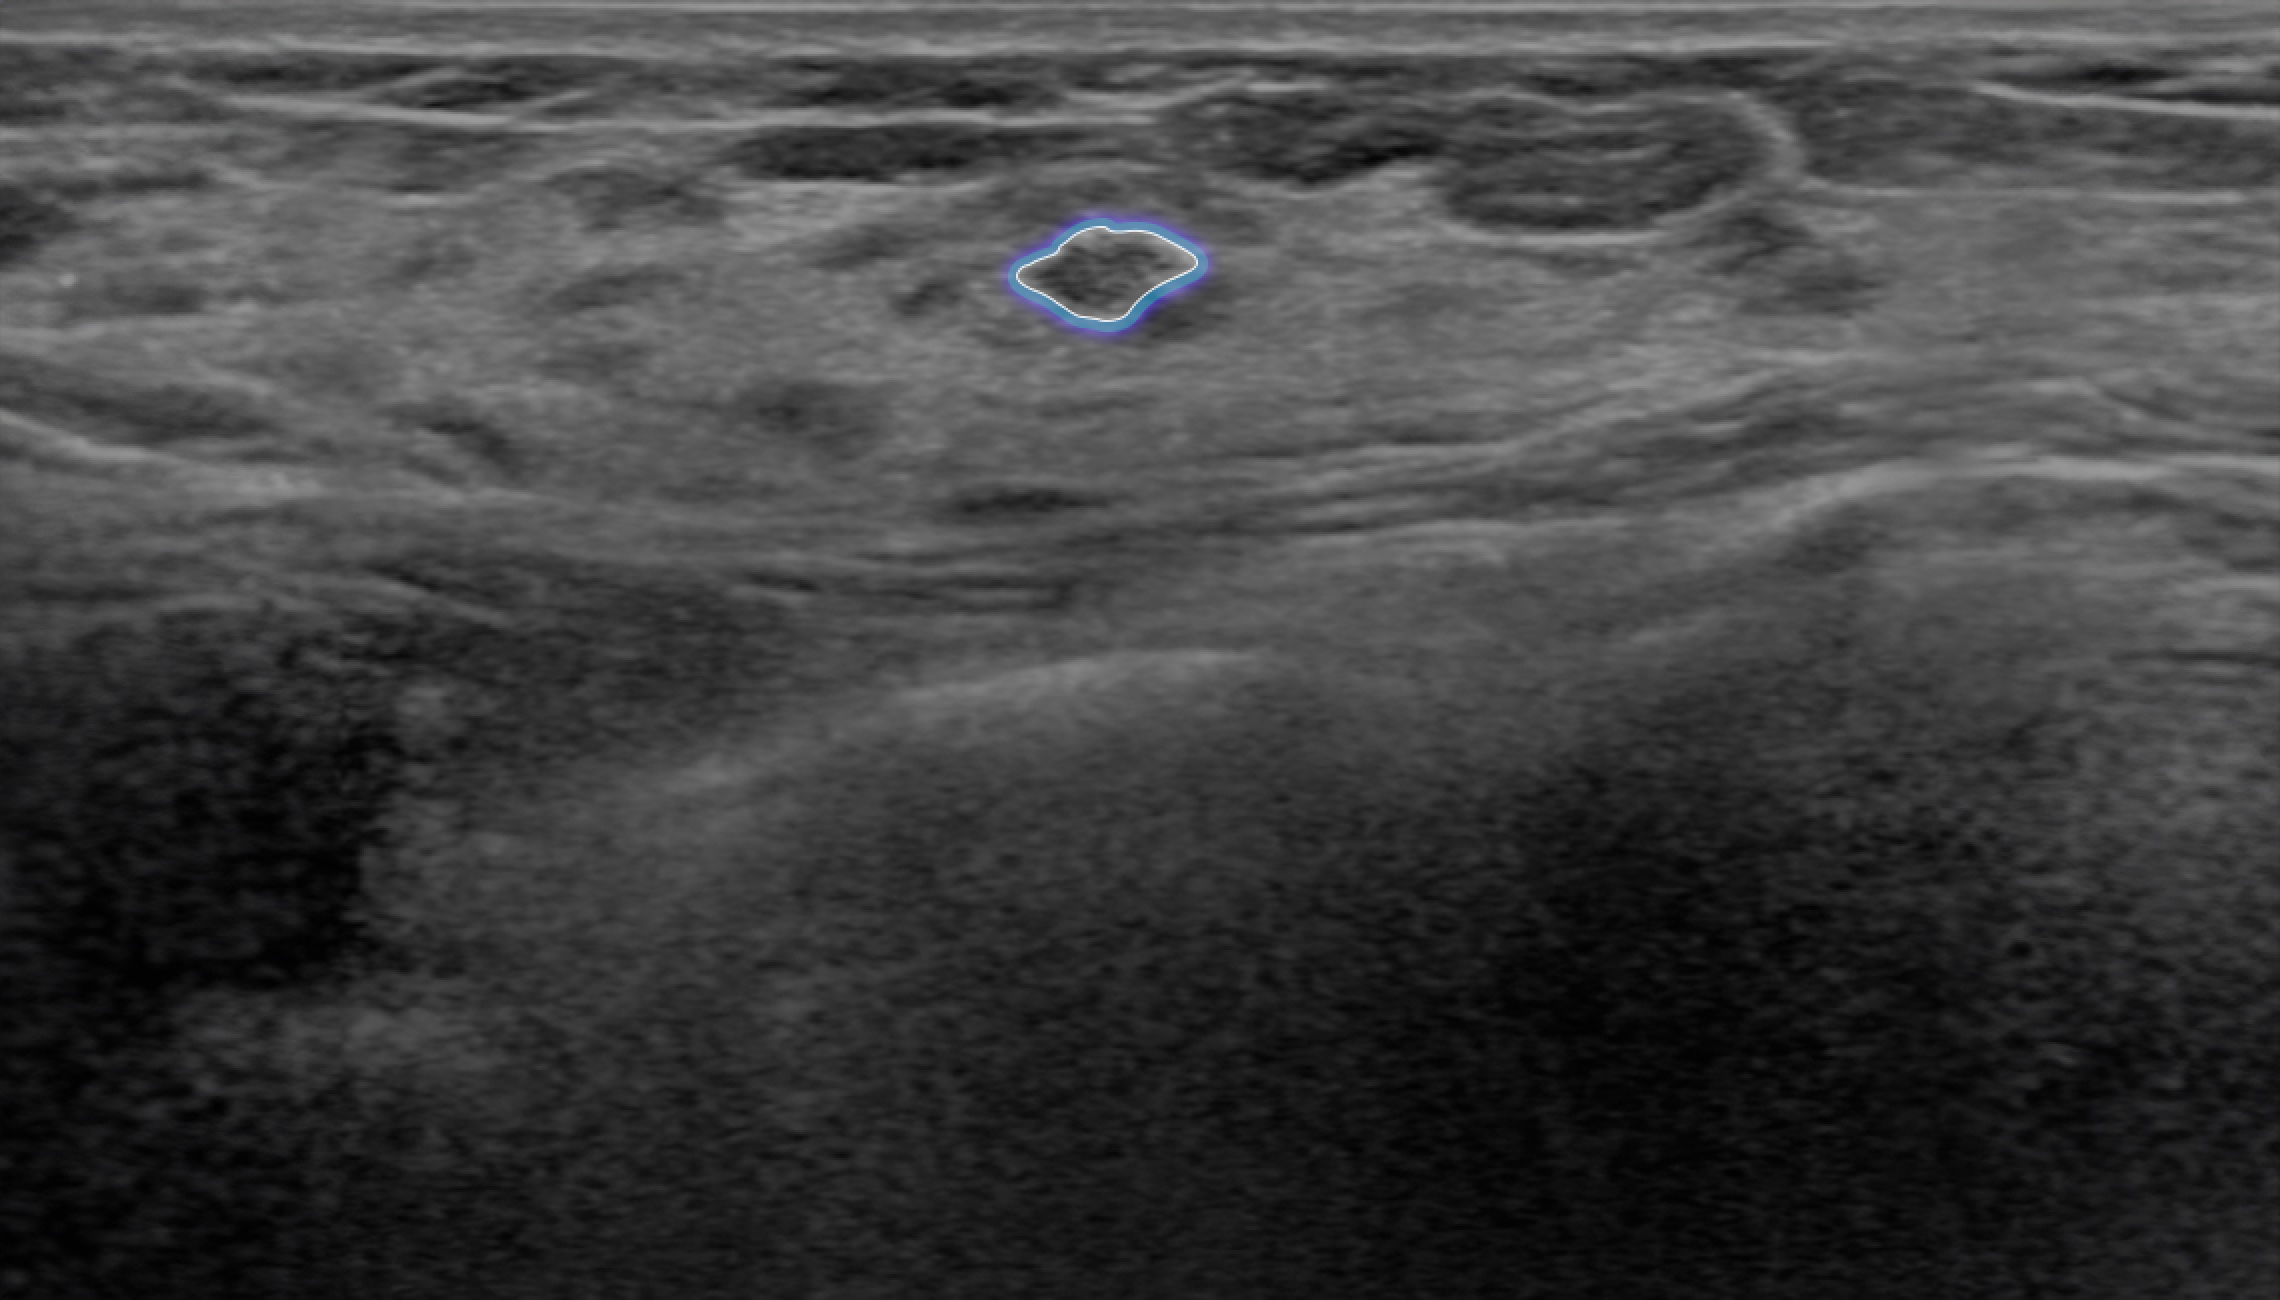

Follow up mode

Automatically matches lesions from previous breast ultrasound examinations, allowing for easy comparison of changes in the lesions.

Analysis Report Provision

Automatically matches lesions from previous breast ultrasound examinations, facilitating a quick and easy comparison of changes in the lesions at a glance.